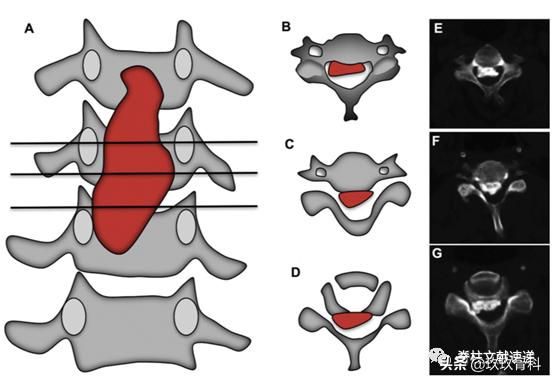

下图所示为骨化块残留情况。

下图所示为骨化块宽度评估,图B为宽基底骨化块,易残留。

术前应仔细阅片,明确骨化块与椎弓根的关系,B、E易切开,D、G易残留。